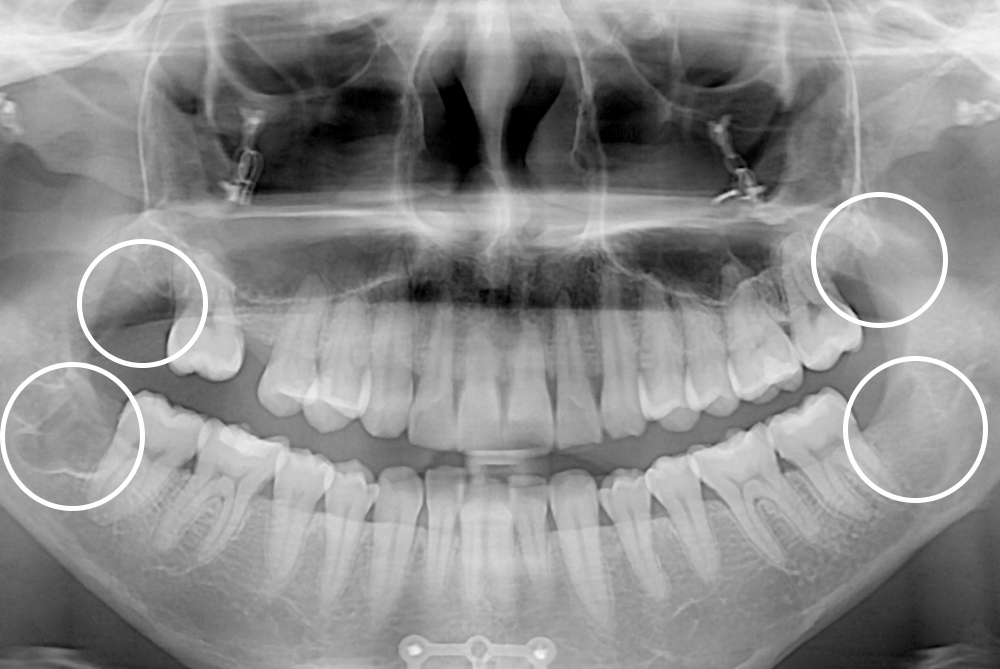

[사랑니] 매복 사랑니 발치

치료전 : 2021-03-09